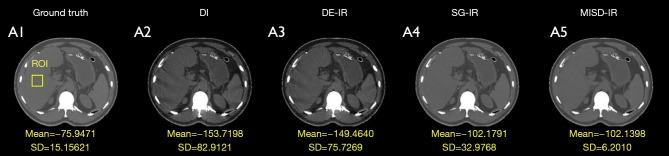

RESULTS

In numerical experiments, the results of MISD-IR were closer to the ground truth compared with other methods. In real scanning data experiments, the results of MISD-IR showed sharper edges and details. Compared with other one-step iterative methods in the experiment, the running time of MISD-IR was reduced by 75%.